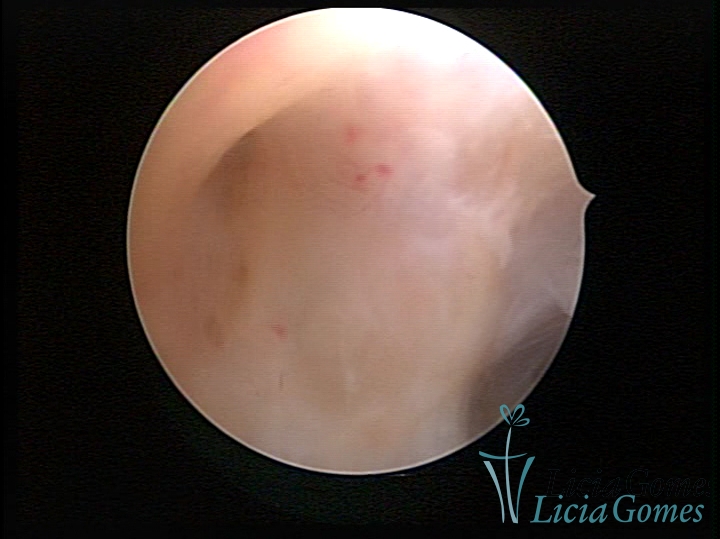

SINÉQUIA TIPO MUCOSA